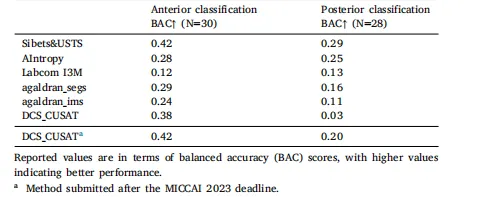

Table 6Results of proposed solutions by each team for Task 1 (classification of the anteriorand posterior CoW variant) on data from another institution (N=30).

表 6 各团队针对任务 1(Willis 环前部和后部变异型分类)在另一机构数据(样本量 = 30)上提出的解决方案的结果